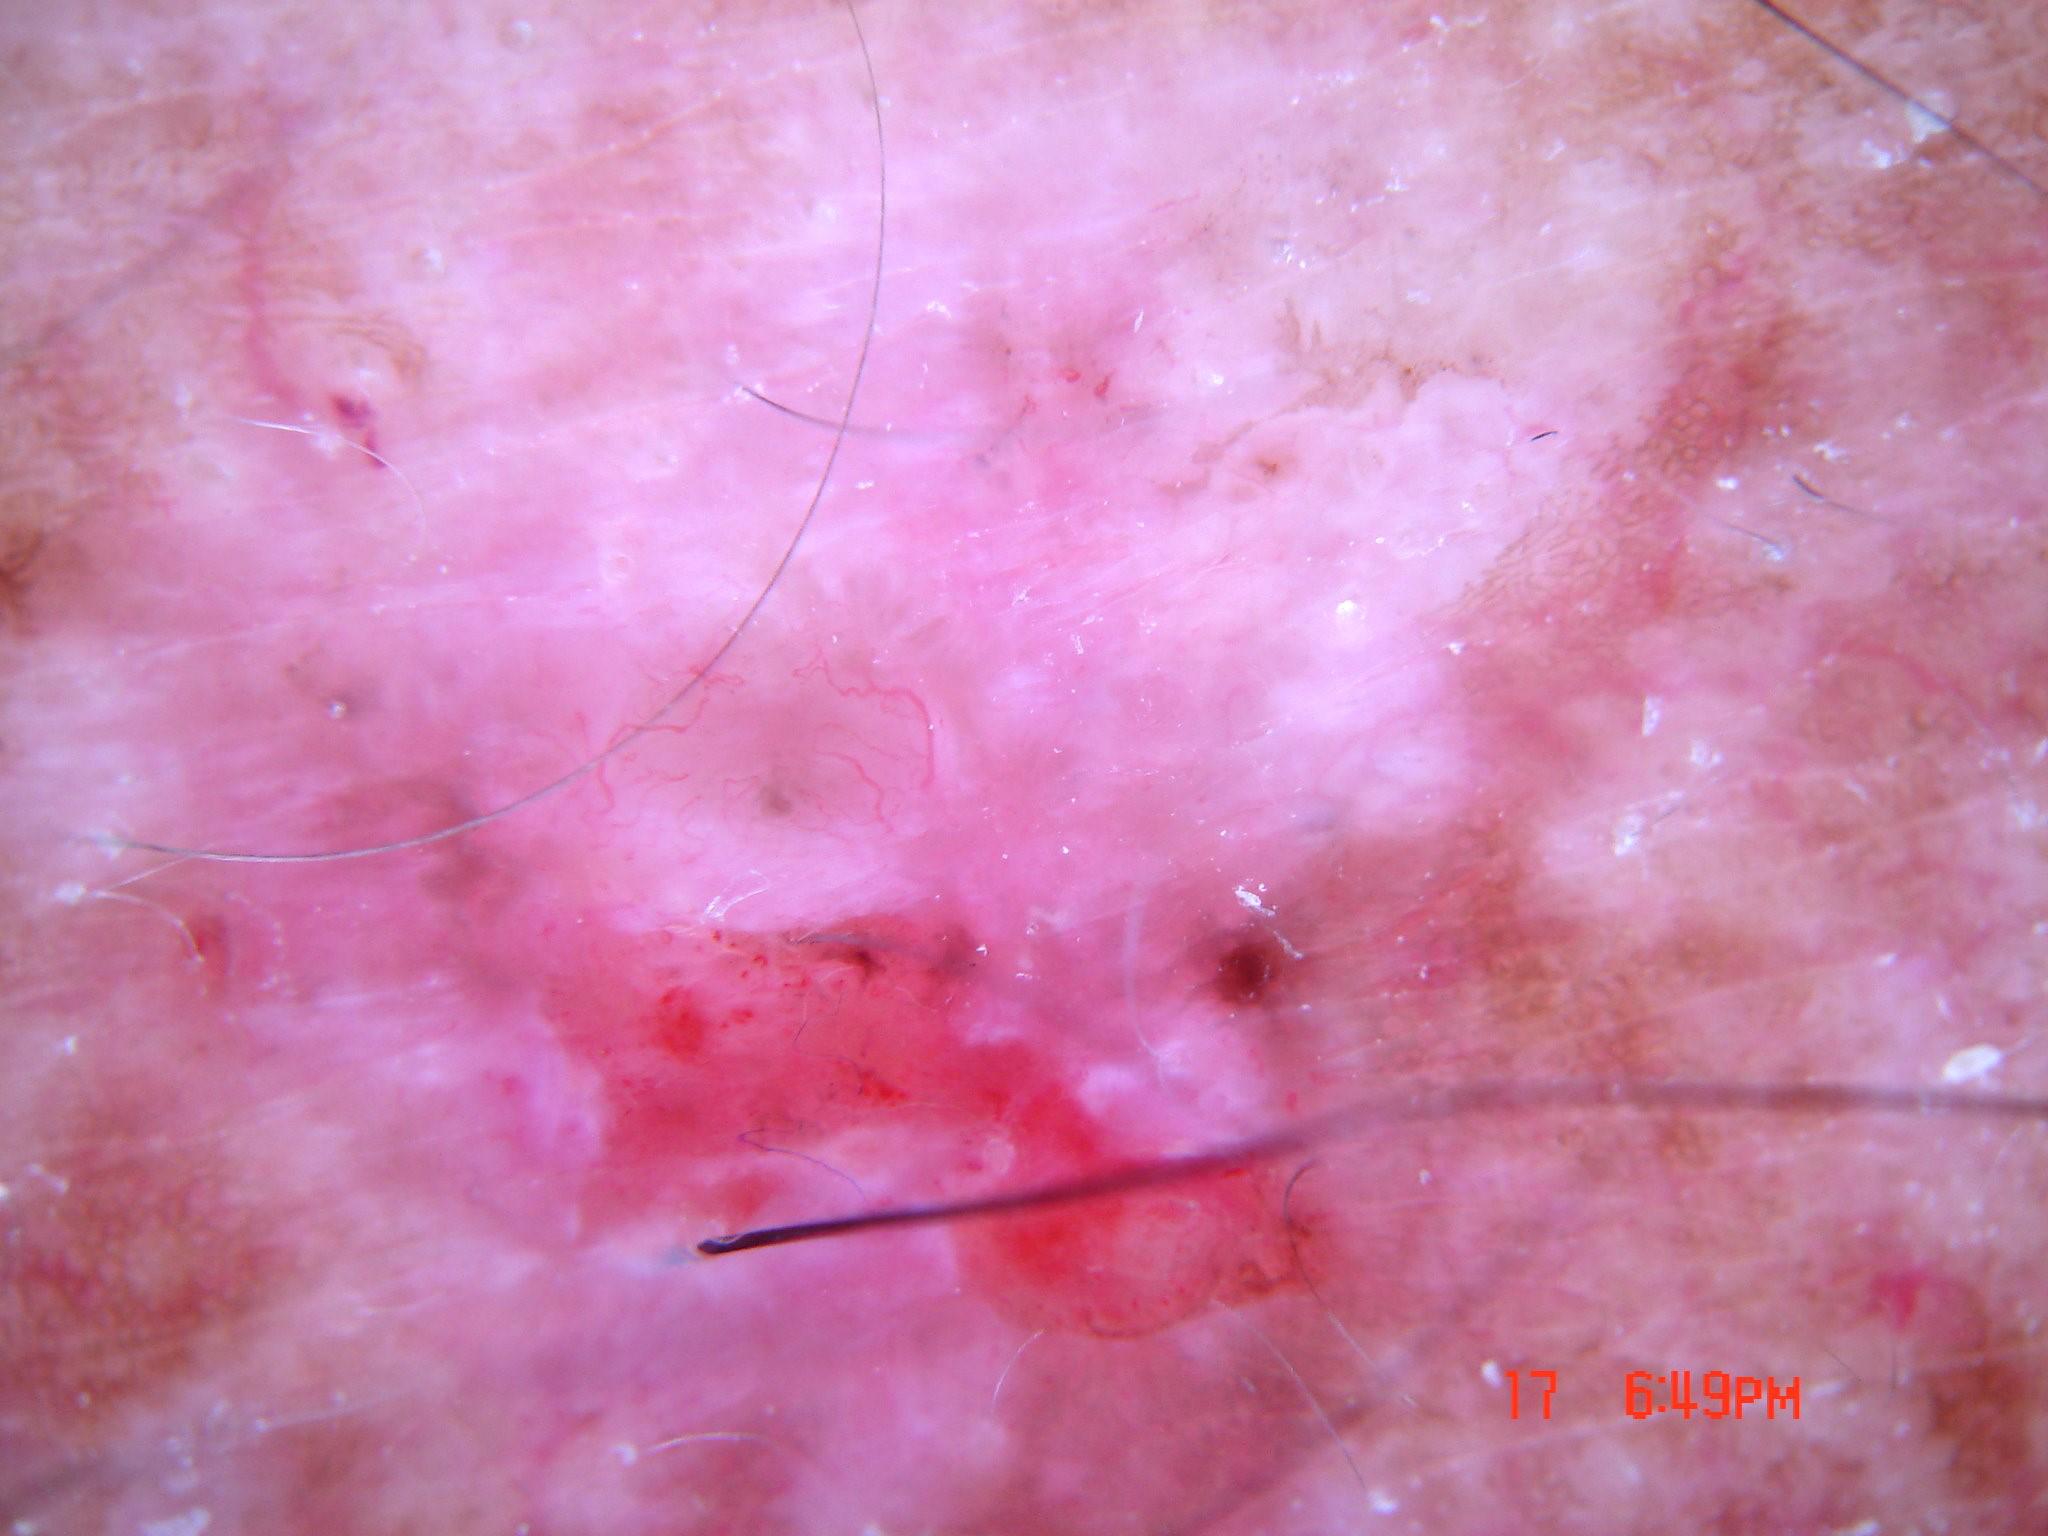

Biopsy-confirmed melanocytic and non-melanocytic skin lesions. This dataset includes over 500 melanomas. Many images have polarized and contact variants.